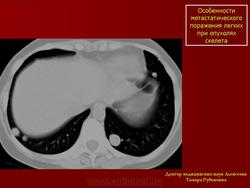

Особенности метастатического поражения легких при опухолях скелета

Наличие в метастазах очагов патологического костеобразования, является характерным признаком остеосарком. Кроме того, неоднородность метастазов может быть обусловлена распадом опухолевой ткани. Образующаяся полость располагается ассиметрично, имеет четкие ровные внутренние контуры.

Остеосаркома бедренной кости. Метастазы в легкие.

Фрагмент комтьютерной томограммы правого легкого: в субплевральном отделе средней доли овальной формы образование с четкими наружными контурами, с ассиметрично расположенной полостью распада в толще. Окружающая легочная ткань не изменена.